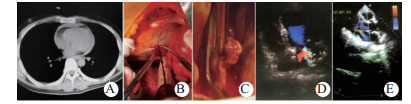

| 图 2 例4紧急剖胸心包减压、心脏修补,剖腹脾切除(A:术前CT示血心包; B、C:心包减压后钳闭左心耳破口; D:术后15 d超声心动图示二尖瓣重度反流; E:术后130 d超声心动图复查示二尖瓣轻度反流) Fig 2 Case 4 having emergency decompression of thoracic pericardium, cardiac repair, and abdominal splenectomy (A: Preoperative CT showed blood pericardium; B and C: Pericardial decompression performed to close the rupture of left auricle; D: Echocardiography showed severe mitral regurgitation on postoperative day 15; E: Echocardiography showed mild mitral regurgitation on postoperative day 130) |